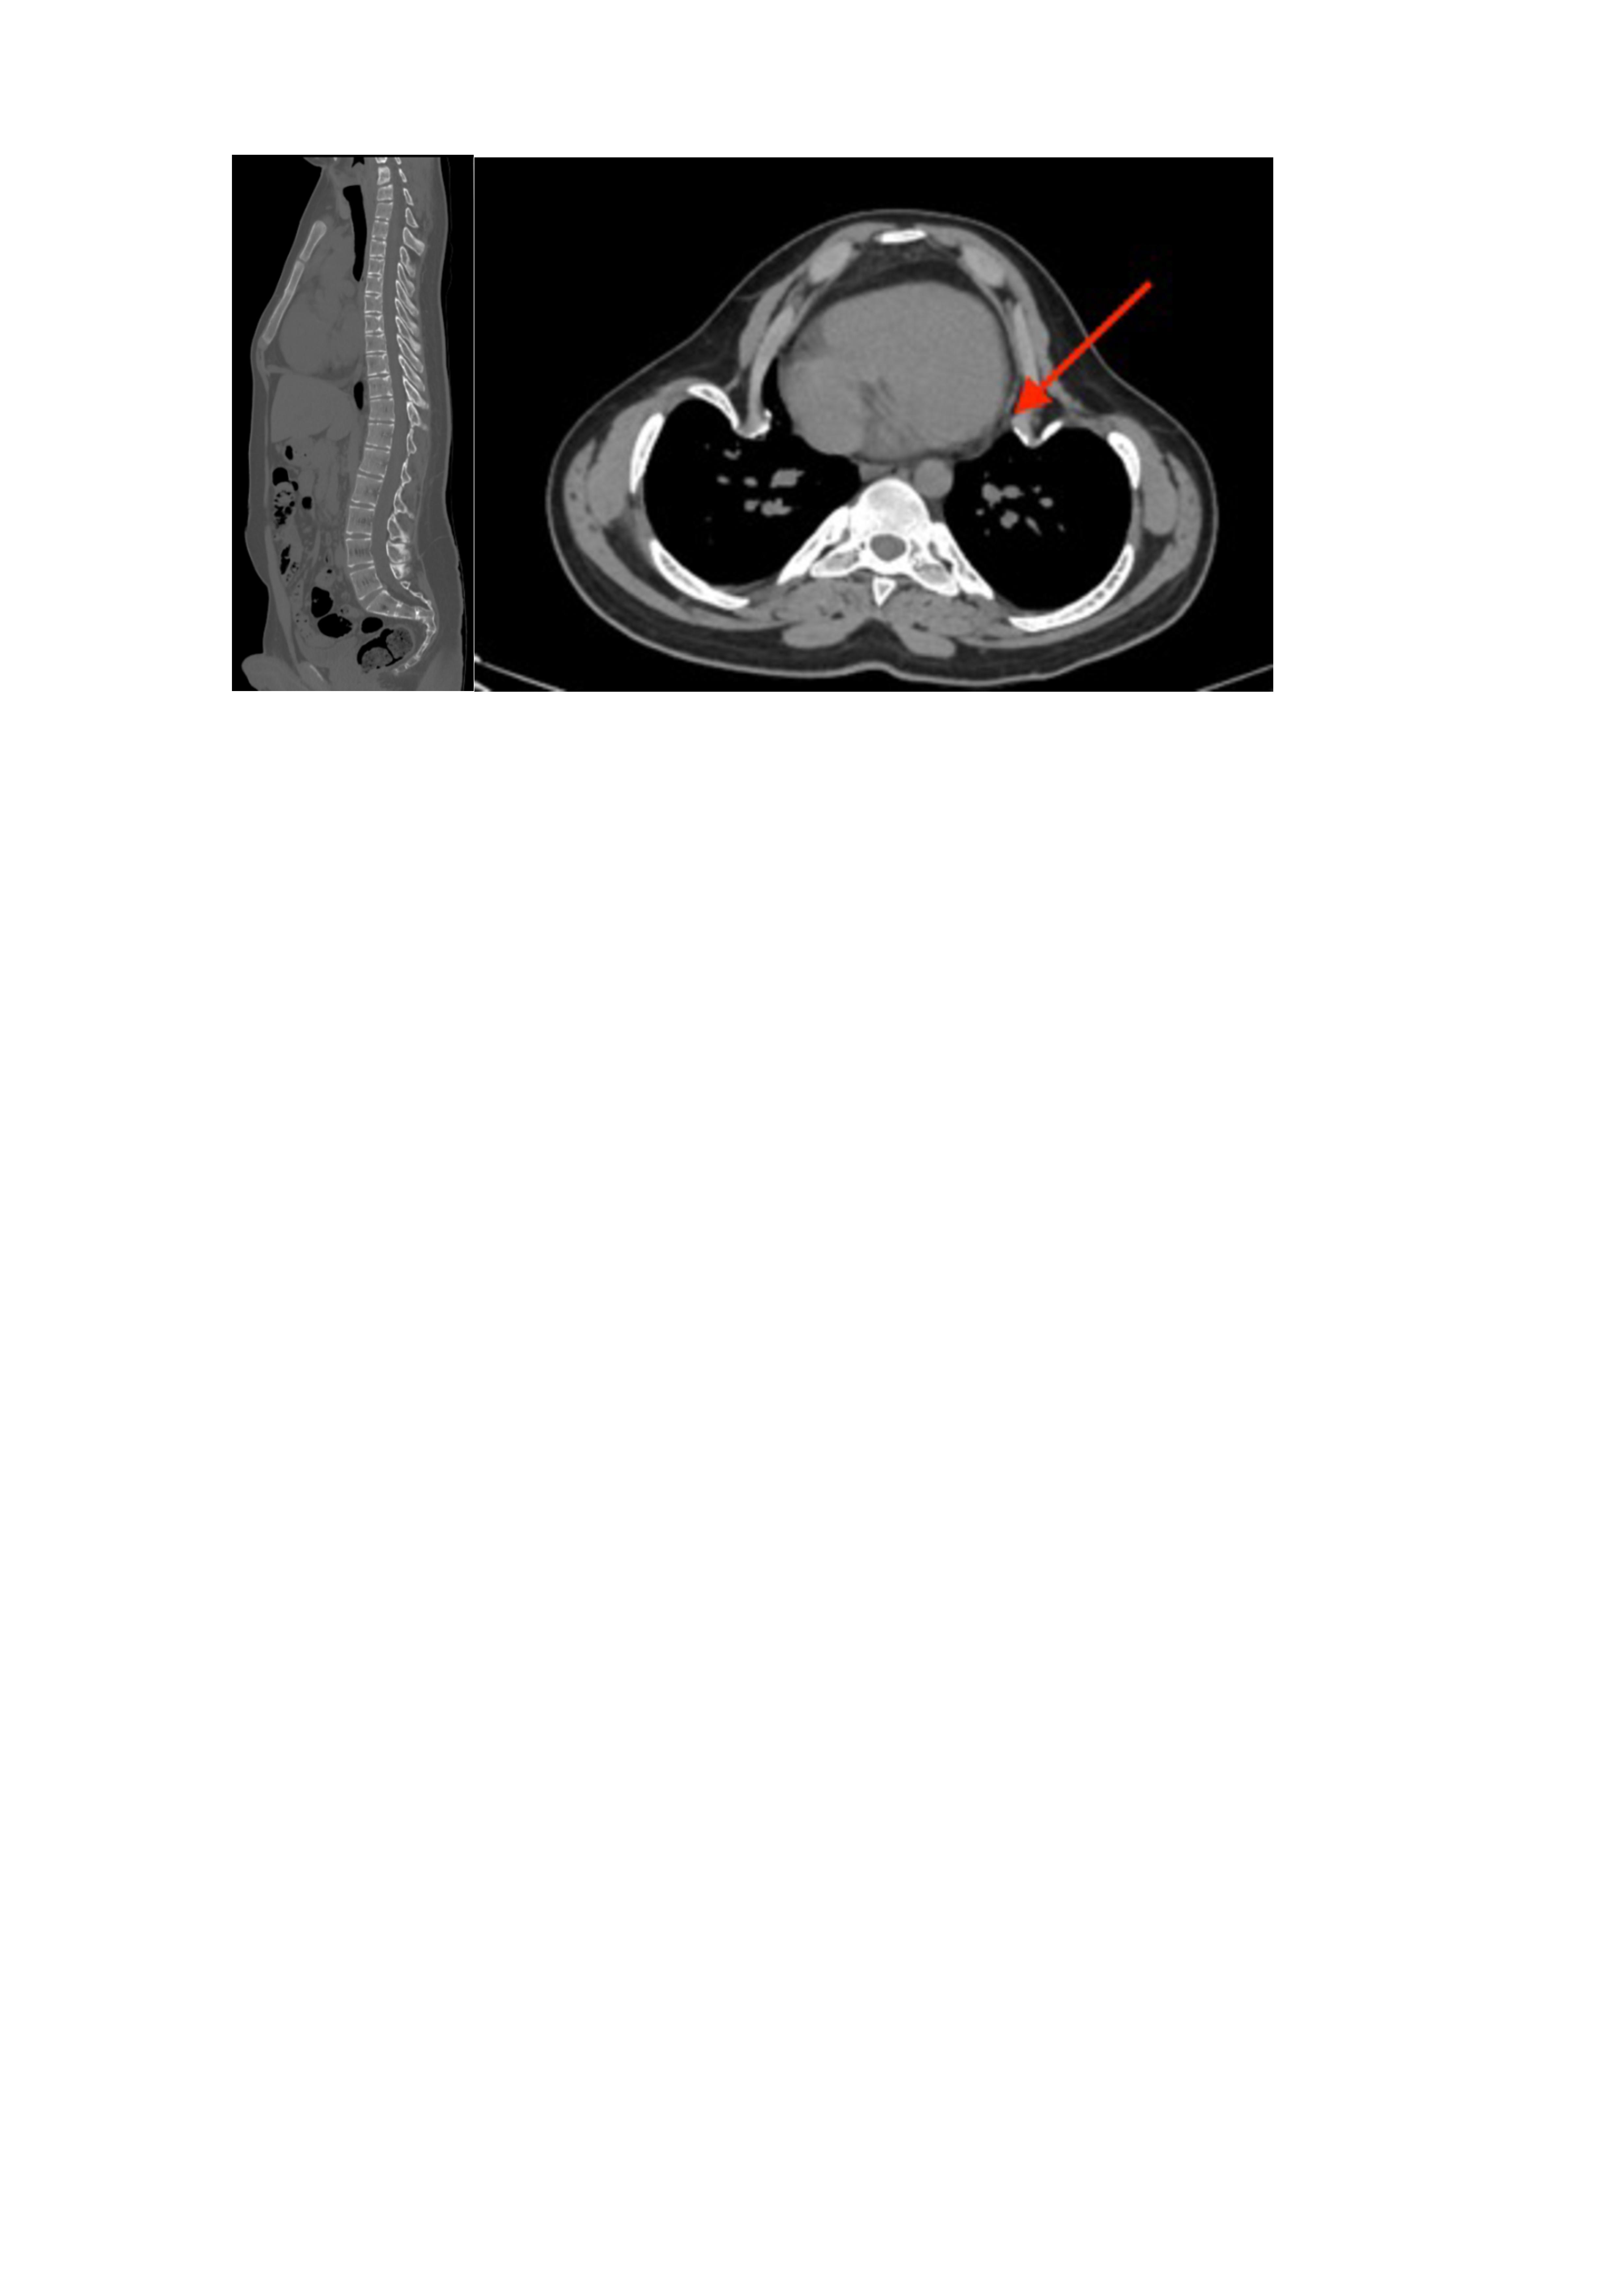

При исследовании состояния костной системы выявлено повышение маркеров костного ремоделирования: остеокальцин – 92,38 нг/мл (норма 24–70), С-концевой телопептид коллагена I типа – 1,39 нг/мл (норма 0,01–0,7). По результатам мультиспиральной компьютерной томографии грудного и поясничного отделов позвоночника отмечается выраженная кифосколиотическая деформация с прилежанием ребер к перикарду правого предсердия (Рис. 2).

Рис. 2. МСКТ грудного и поясничного отделов позвоночника.

Описание: выраженная кифосколиотическая деформация с прилежанием ребер к перикарду правого предсердия.